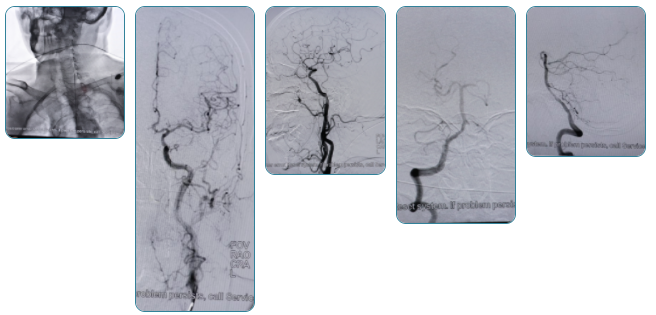

2022年10月13日,在院领导的大力支持下,琼海市中医院神经内科(脑病科)林道强主任带领的介入医疗小组自主独立开展首例全脑血管造影术,取得了圆满成功。这填补了我院脑血管病介入诊疗技术的空白,标志着我院在脑血管疾病的诊断方面迈出突破性的一步,为提高我院综合实力迈出坚实的一步。此项技术的成功开展,为广大患者带来了福音。

本次主刀医生为我院神经内科(脑病科)李照学主治医生,于2021年9月至2022年9月在首都医科大学宣武医院进修神经介入,这是他学成归来后开展的首例脑血管造影术,技术过硬,过程顺利。

据了解,全脑血管造影术是诊断脑血管疾病的“金标准”,同时也是颅内血管疾病介入治疗的基础和前提。通过DSA能清晰地显示脑血管疾病及血流的变化情况。它具有创伤小、安全性高、诊断清楚、恢复快等特点,适用于颅内血管病变、颅内占位性病变、颅脑外伤引起的脑血肿等病症,也可用于术后观察手术效果及脑血循环。

全脑血管造影术是一种常规的、成熟的诊断方法,通过手腕的桡动脉,或者通过大腿根部的股动脉穿刺,置入一根导管,在X光引导下将导管插入供应脑部的相应动脉里,通过注入造影剂,根据血管显影的形态和部位来诊断脑血管疾病。整个过程在局麻下完成,操作时间短,但作用不可替代。

是诊断脑血管病的金标准,可以直观的显示所观察血管的整体情况,包括其形态、周围比邻血管位置、血管内径、血流方向及灌注,经过处理可得到3D图像,更利于判断血管情况,如:动脉狭窄、动脉闭塞、动脉瘤、血管畸形等,有助于我们对病变血管的全面了解,为制定下一步治疗方案提供可靠依据。